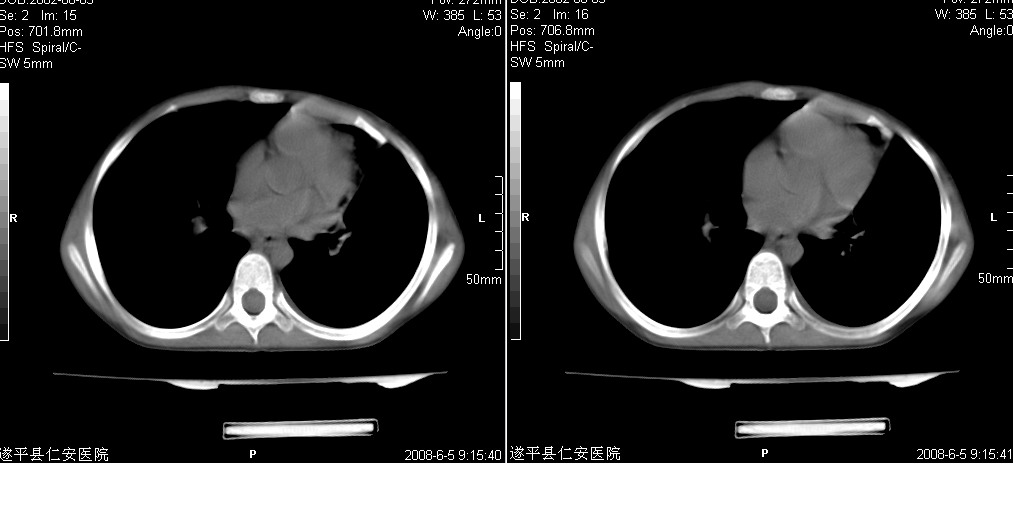

以下是引用xxhwh在2008-6-10 18:40:00的发言:[br]男,6岁,无规则发热一月余,体温在37.8——39度之间。一月前拍胸片示左上肺密度增高影,进行抗炎治疗8天,复查胸片未明显吸收。又改变抗菌素继续治疗半月,照胸片示病灶吸收不明显,行ct检查[br]征象:左上肺前段呈密实影,内可见支气管气像,远侧见絮状模糊影,中上纵隔左移。[br]意见:左上肺前段膨胀不全及感染,考虑为支气管异物或支气管内膜结核所致,[br]建议追问有无异物吸入史,行痰检及ppd检查